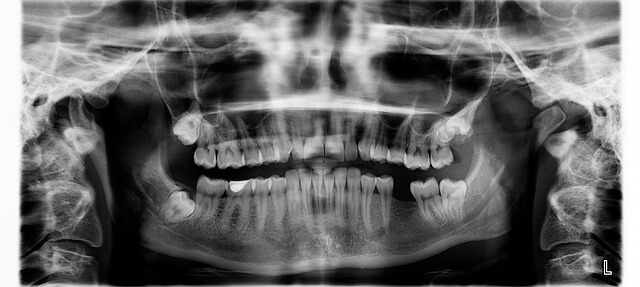

불소도포 원리와 치아 보호의 과학

불소도포란 불소 성분을 치아 표면에 바르는 방법으로, 치아의 겉면인 법랑질을 단단하게 만들어 줍니다. 이 과정은 충치를 일으키는 산이 법랑질을 약화시키는 것을 막아주는 역할을 하죠. 제가 실제로 불소도포를 받았을 때 느낀 건, 치아가 미끄럽고 매끄럽게 변한다는 것이었어요. 바로 그 표면 강화 효과 덕분입니다. 이런 변화는 며칠이 지나면 자연스럽지만, 내부적으로는 치아가 산에 훨씬 강해집니다.

치과 의사들도 말하길, 불소는 칼슘과 결합하여 더 단단한 ‘불화인회석’을 형성한다고 해요. 이게 바로 불소도포의 핵심 과학적 원리입니다. 유아기부터 시작하면 성인기까지 충치 예방 효과가 크게 올라가기 때문에 조기 관리가 중요합니다.